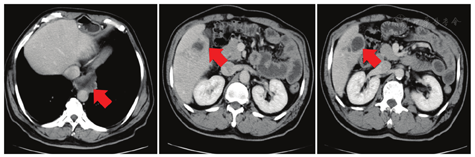

术后ECOG PS评分为1分,因患者拒绝静脉化疗,2018年8月10日至2018年9月21日术后外院行替吉奥60 mg每天早、晚餐后半小时口服,连续口服14 d,每21天为一周期,共化疗2个周期。2018年10月23日复查全身PET-CT示:右侧锁骨上、右侧颈部Ⅳ区、右侧颈部喉返神经旁、降主动脉旁、脾动脉近端近腹腔干多发淋巴结转移,肝S5转移。患者未行治疗。1个月后胸腹盆CT提示降主动脉旁淋巴结转移灶及肝转移灶较前增大(见图1),予紫杉醇脂质体270 mg第1天静脉滴注+顺铂50 mg第1天、40 mg第2~3天静脉滴注,每21天为一周期,共化疗2个周期,2个周期后评价疗效为疾病进展(见图2)。程序性细胞死亡配体1(PD-L1)检测(原手术组织,抗体型号22C3)结果为高表达,肿瘤细胞阳性比例分数(TPS)为80%。2019年2月15日给予帕博利珠单抗注射液200 mg第1天+伊立替康400 mg第2天,每21天为一周期,治疗1个周期。1周后患者出现黄疸,肝功能示:丙氨酸氨基转移酶(ALT)68.6 U/L,总胆红素(TBIL)89.7 μmol/L,直接胆红素(DBIL)83.7 μmol/L。予多烯磷脂酰胆碱注射液等药物治疗后黄疸进一步加重,复查肝功能示:ALT 32.5 U/L,TBIL 235.3 μmol/L,DBIL 215.5 μmol/L;MRI示肝内多发结节部分融合成团,边界不清,肝门部软组织肿物沿胆道系统向肝内蔓延生长,肝内胆管扩张在肝门部截断,胆总管显示不清,考虑转移瘤累及肝门、胆总管。胆囊周围、腹腔及腹膜后、上腔静脉与主动脉间多发结节及肿物,部分融合,大者约6.6 cm×5.1 cm,考虑淋巴结转移。磁共振胰胆管成像(MRCP)示肝内胆管呈"软藤状"扩张,并在肝门部截断,胆总管及胰管显示不清,胆囊显示不清(见图3)。